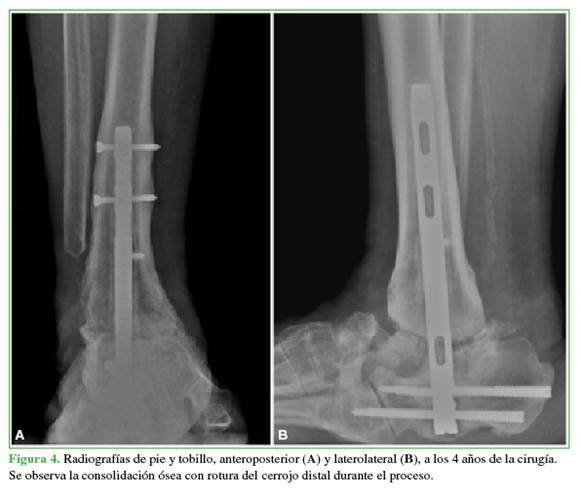

Al final del seguimiento, 7 pacientes tenían una consolidación estable de la artrodesis TTC (Figuras 3 y 4), dos desarrollaron una consolidación fibrosa que les permitió la deambulación con un equipamiento ortésico. Uno requirió una revisión tardía de la artrodesis y aún está en el período de seguimiento. La mediana de tiempo de consolidación fue de 8.6 meses (RIC25-75%: 4.7-8.6).